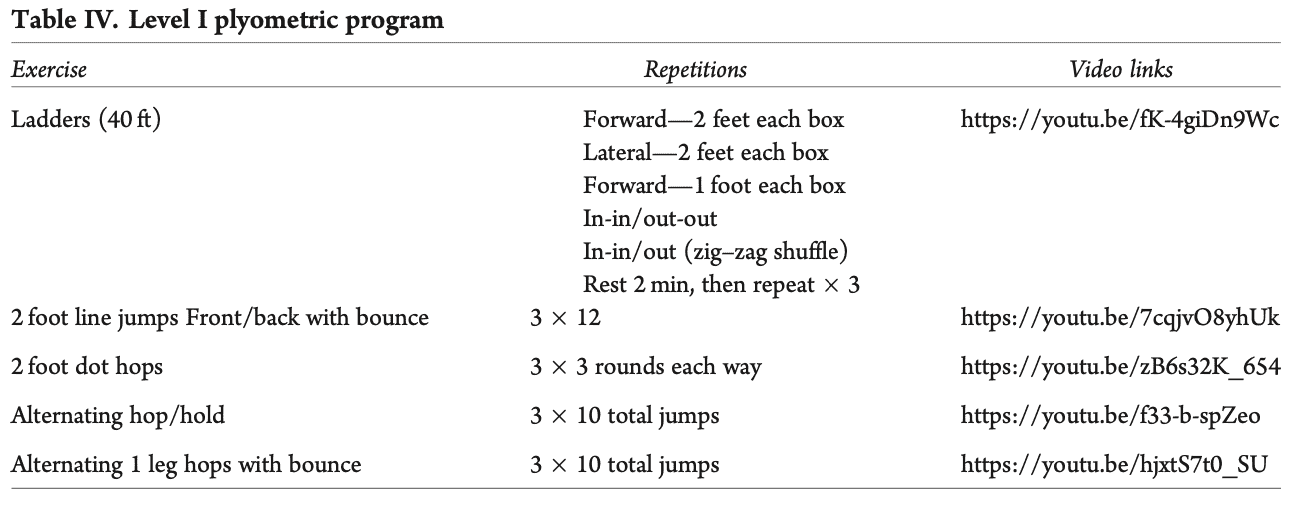

- Фаза 2 беше бърза реакция и плиометрична дейност. В тях се посочва следното: "Бързата мускулна реакция и плиометрията започват в тази фаза, като се стига до около 500-600 контакта между единия и двата крака. Така, ако средният оборот на бегача е 170-180 крачки в минута, за да достигне необходимите 500-600 контакта с един крак, ще е необходимо да бяга 5-7 минути."